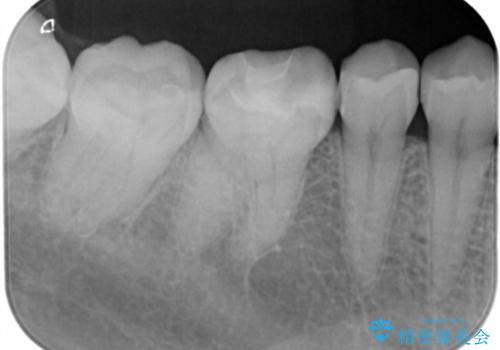

- 右下6番のメタルインレー脱離のため来院。

セラミックの治療を希望されたため切削量を考慮し、セラミックインレーでの治療を選択しました。

う蝕が深くまで進行していたので、CRで裏層した上で形成・印象をしています。